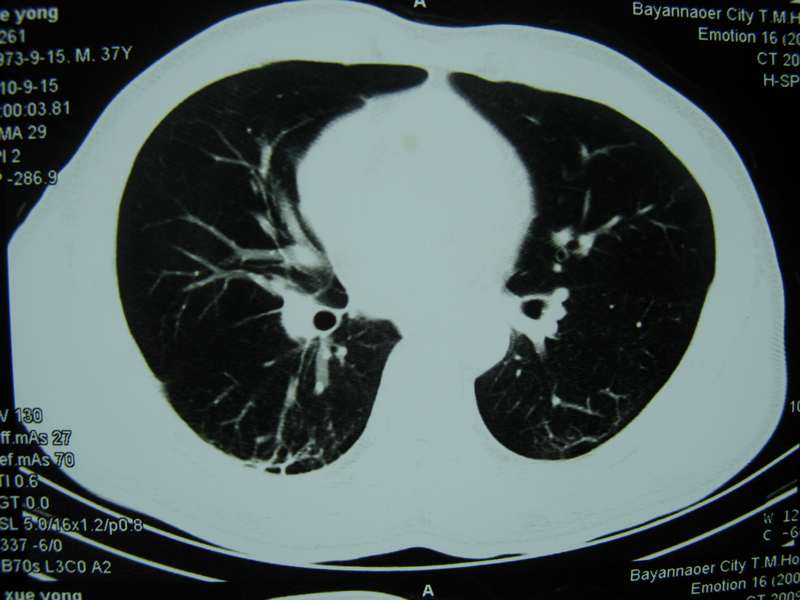

男,37岁,主述胸疼厉害,无咳嗽,无发热,血象也不高,病灶内ct值脂肪密度,右侧胸腔内少量积液,同道们考虑什么?谢谢!

两肺下叶基底段纤维灶,右肺下叶基底背侧相应胸膜肥厚,右肺中叶内侧段部分不张。前中下纵隔团块状脂肪影,随访除外胸腺脂肪瘤。